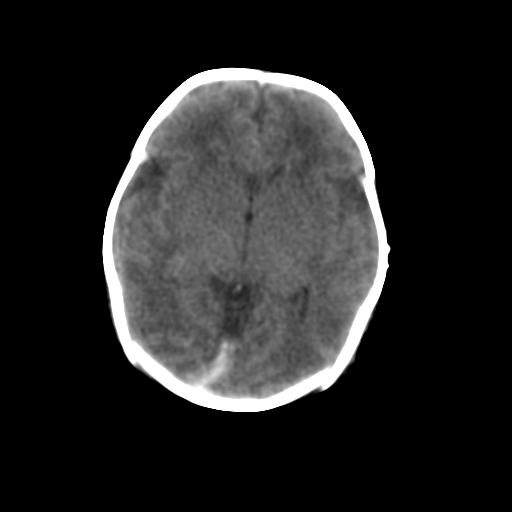

新生儿女2天,有窒息史,经抢救好转!白质最低ct值>23hu,请教各位老师:是否有出血?是否合并缺氧脑病?谢谢!

hie、蛛网膜下腔出血,皮下血舯。

hie、蛛网膜下腔出血,皮下血舯。透明隔间腔形成支持

双侧额叶白质低,白质ct值低于18hu可以考虑水肿改变

后纵裂密度高,前纵裂密度低,比较来说应该考虑有蛛网膜下腔出血

空三角征,蛛网膜下腔出血。